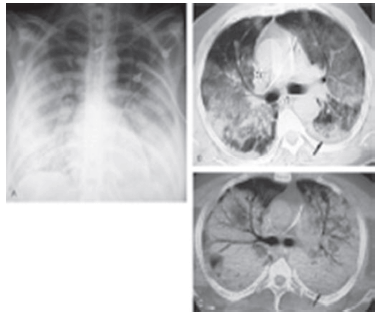

Um paciente de 48 anos foi admitido na UTI com história de uma forte gripe até uma semana atrás. Apresentava síndrome febril, tosse, dispnéia; há uma hora, apresentou hipotensão arterial. Baseado na história e na imagem, podemos afirmar o diagnóstico de:

O conjunto de imagens abaixo representa o diagnóstico de: